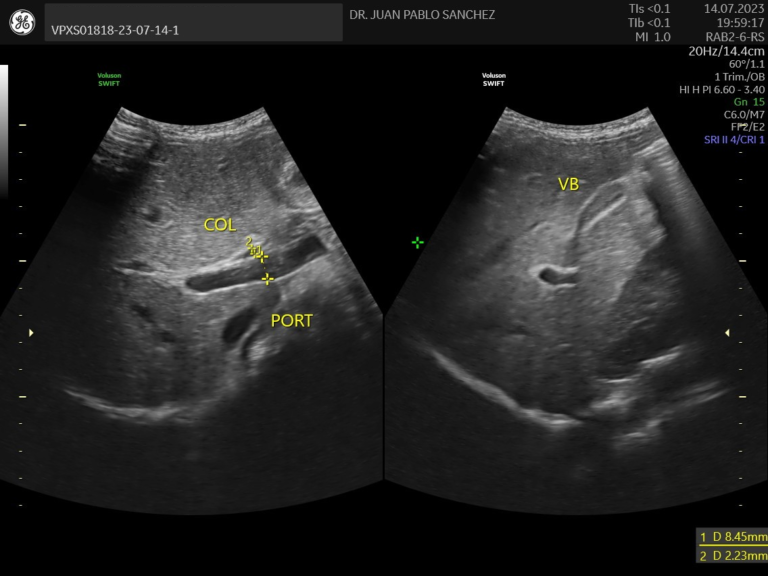

Ecografia abdominal

Estudio no invasivo que permite observar los órganos del abdomen, como el hígado, riñones, intestinos, vejiga, etc. Es útil para detectar infecciones, malformaciones o dolores sin usar radiación ni dolor.